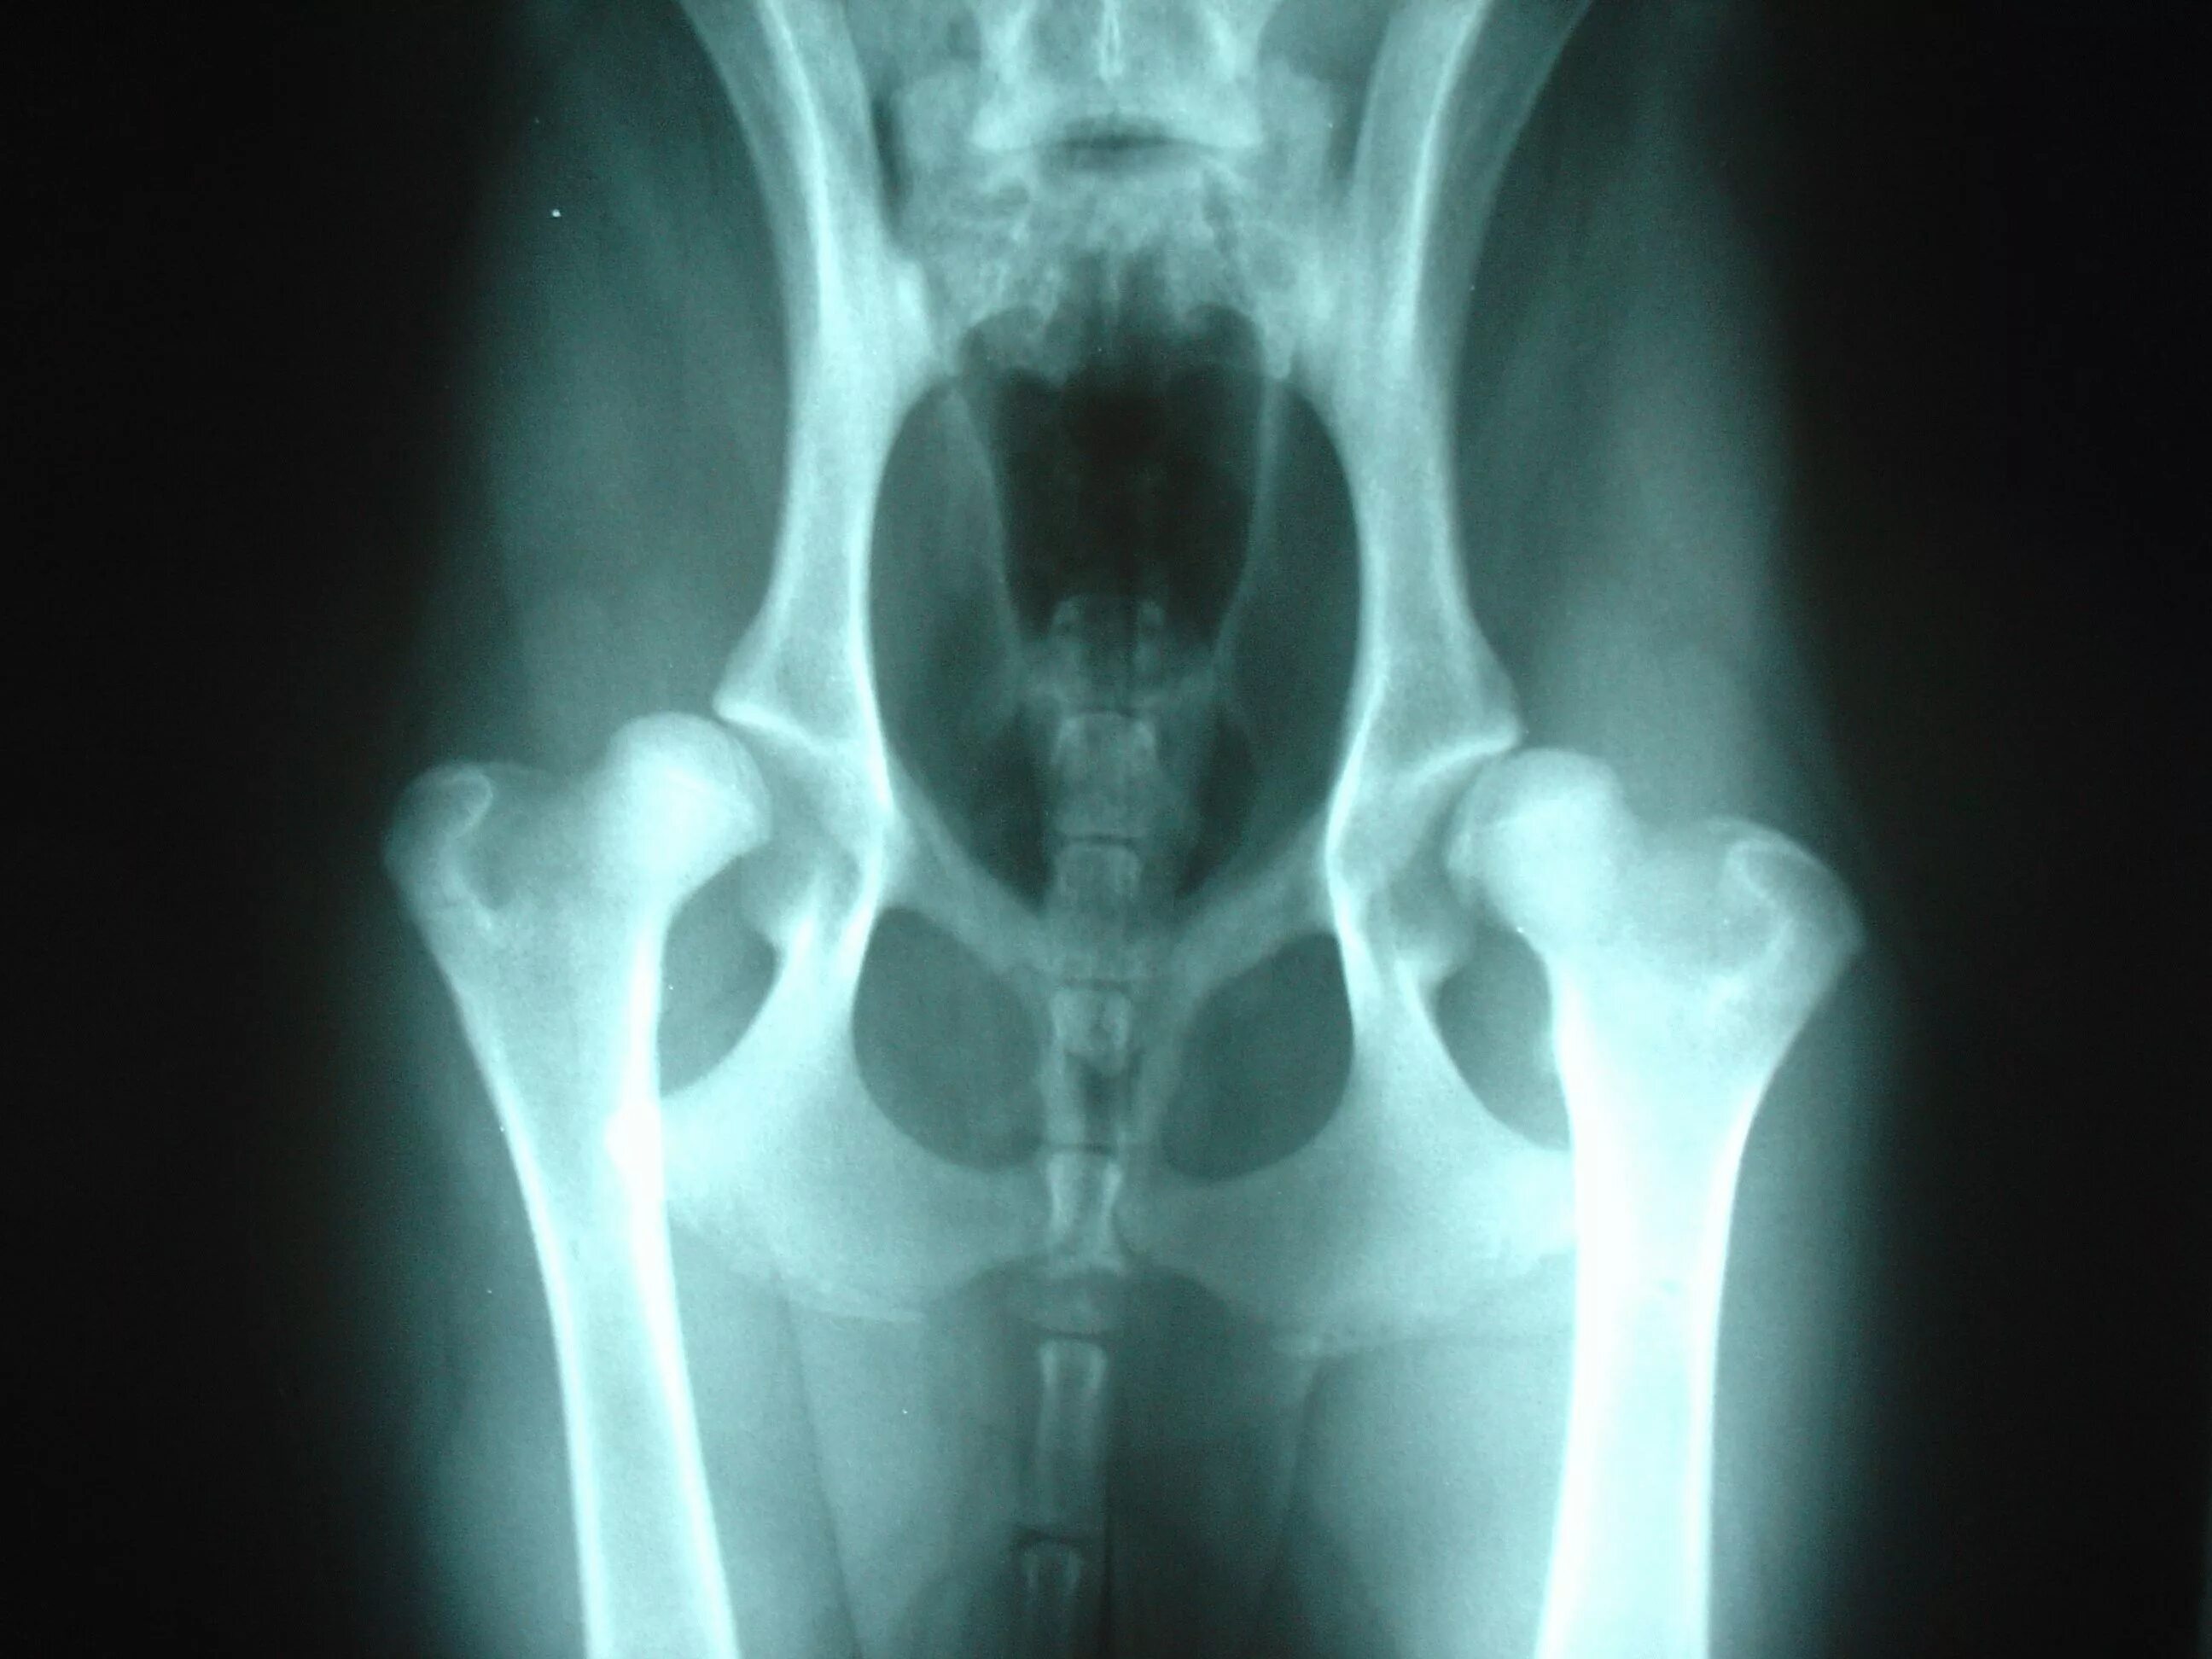

Лечение тазобедренного сустава у собак